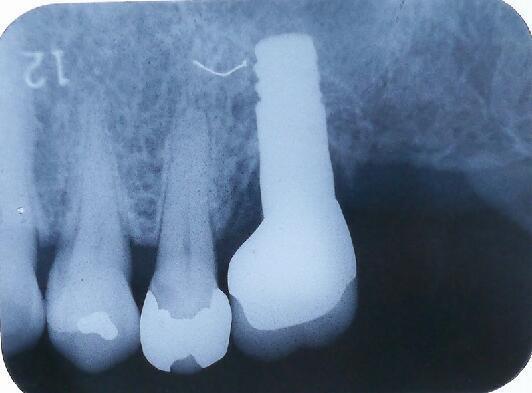

オペ当日のエックス線写真です